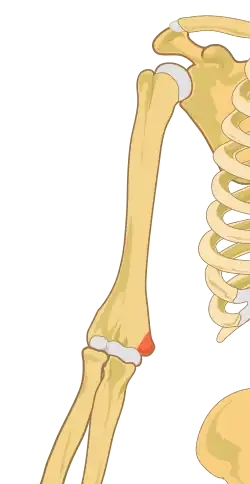

Epicôndilo medial do úmero

O epicôndilo medial do úmero é uma eminência localizada na extremidade distal do úmero, próximo à articulação desse osso com a ulna. É maior e mais proeminente do que o epicôndilo lateral. É onde se localiza o tendão comum que origina os músculos palmares antebraquiais superficiais, que são o pronador redondo, o flexor radial do carpo, o palmar longo, o flexor ulnar do carpo e o flexor superficial dos dedos. O epicôndilo ainda dá inserção ao ligamento colateral ulnar da articulação do cotovelo.[1]

O epicôndilo medial do úmero em seres humanos é maior e mais proeminente do que o epicôndilo lateral e é direcionado ligeiramente mais posteriormente na posição anatômica. Em aves, em que o braço é ligeiramente rotacionado comparado a outros tetrápodes, é chamado de epicôndilo ventral do úmero. Em anatomia comparada, o termo mais neutro entepicôndilo é usado.[2]